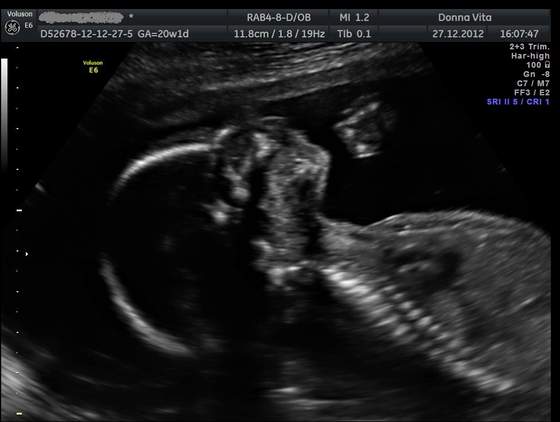

Po świętach w Lublinie u rodziców stwierdziliśmy, że pójdziemy sobie na USG 3D/4D bo tam jest więcej wyspecjalizowanych gabinetów niż w mieście w którym mieszkamy. Gin pomierzył wszystko dokładnie i serduszko ok, główka, mózg, kręgosłup i inne ważne rzeczy również. Dzidzia jest o 5 dni młodsza niż według OM, ale Gin pytał się mnie ilu dniowe miałam cykle i że wszystko jest w porządku. W trakcie pyta się czy chcemy znać płeć, a my, że oczywiście, więc mówi : JEST FUJARKA I SĄ JAJKA

Czyli moje przeczucia co do płci się sprawdziły. Mamy piękne zdjęcie synka od dołu, który pokazał się w całej swojej okazałości:-)

Dostaliśmy wydruk kilku zdjęć oraz chyba 4-5 filmików, jest taki piękny, już jestem zakochana po uszy!